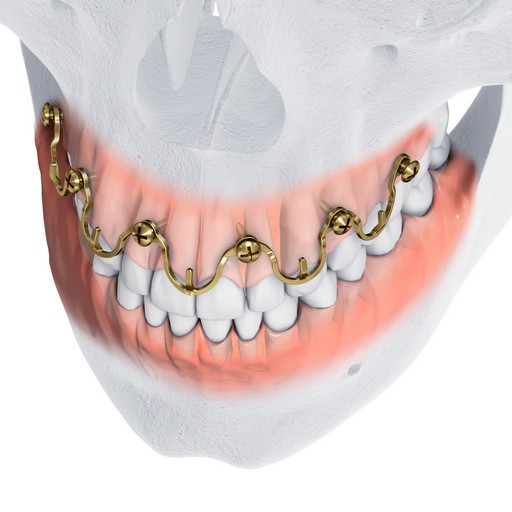

MatrixWAVE MMF (Figs 1-8) is a novel bone-borne MMF system that combines the strength and rigidity of arch bars with the speed and simplicity of IMF screws. It consists of a wave shaped plate that is attached to the mandible and maxilla with self-drilling locking screws (Fig 3). The plate is adaptable and can be extended horizontally (Fig 4) to allow screw hole placement in the optimal location to avoid tooth roots and nerves. The locking mechanism avoids compression and ischemia by keeping the plate away from the mucosal tissues.

Following application and wiring, the wave plate pattern allows the alignment of bone segments to be adjusted by crimping without repositioning the screws. The plate is available in two heights to allow the positioning of the hooks at the level of the tooth equators according to individual patient anatomy, and to accommodate the use of rigid internal fixation (Fig 2).

A 28 year old white male was subject to personal assault, and sustained a left mandibular angle fracture (Fig 1). The fracture was prestabilized with the Matrix Wave system and then fixated with a 4-hole miniplate 2.0 on the superior border and a 4-hole angulated universal fracture plate 2.4 along the inferior border. A pre-existing anterior open bite was noted and confirmed with the patient prior to presentation to the operating arena.

The MatrixWAVE plate was attached to the maxilla with screw placement in the inter-root spaces (Fig 2). A second MatrixWAVE plate was attached in corresponding position to the mandible, with screw placement in the inter-root spaces (Fig 3). Wires were placed around the plate hooks to bring the dental arches into occlusion. Note the preexisting anterior open bite (Fig 4). Careful adjustment of the MatrixWAVE plate and wiring in the region of the mandibular fracture allowed the bone fragments to be precisely aligned without the requirement for screw repositioning (Fig 5). The postoperative panoramic x-ray (Fig 6) shows the two MatrixWAVE plates in situ, with other plates used to fixate the left mandibular angle fracture. Note that a portion of the Matrix- WAVE plate was removed from the left molar region in the mandible (Fig 6).